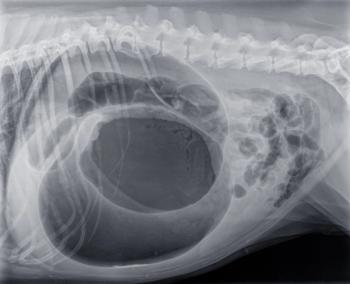

Methods for dealing with GDV, from triage through the initial recovery period, were discussed during a session at the Fetch dvm360 Conference in Atlantic City.